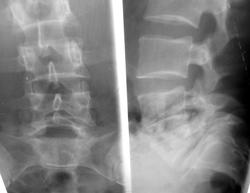

молодой человек,пришел с жалобами на боли в пояснично-крестцовом отделе позвоночника,травму сначала отрицал,но потом вспомнил,что пару лет тому  назад падал,но к врачу тогда не обращался.

имеется спондилолистез L5. Остеохондроз диска L5-S1 и почему-то видится компрессионный перелом тела L5.

а есть в наличии снимки с захватом верхних поясничных позвонков? Чтобы подсчитать количество поясничных позвонков. Может тут диспластическое развитие пояснично-крестцового перехода. Ну и конечно присутствует передний спондилолистез предполагаемого L5 позвонка.

мне вообще видится линия просветления в пятом поясничном-как будто передний его отдел смещен кпереди,а задне-верхняя часть и ост. отросто смещены вверх немного...эта линия на всех снимках повторяется..а не может ли тут быть врожденного какого-то расщепления тела позв.?

Жаль, товарищ Ёжов ничего не написал. smiley Антелистез L5, истинный.

3. Вероятно наличие врожденной аномалии - переходного L5-S1 позвонка, но для точности необходимо выполние 2 пункта.

имеется спондилолистез L5.

вопрос а L5 что-то я сомневаюсь. по расположению похоже S1 c люмбализацией  покажите боковую проекцию полностью

Перелома нет (если не верите повторите прицельно). Есть спондилолиз L5 и антелистез I  ст. и некоторая ротация L4 L5; остеохондроз L4-5-S1 тоже.